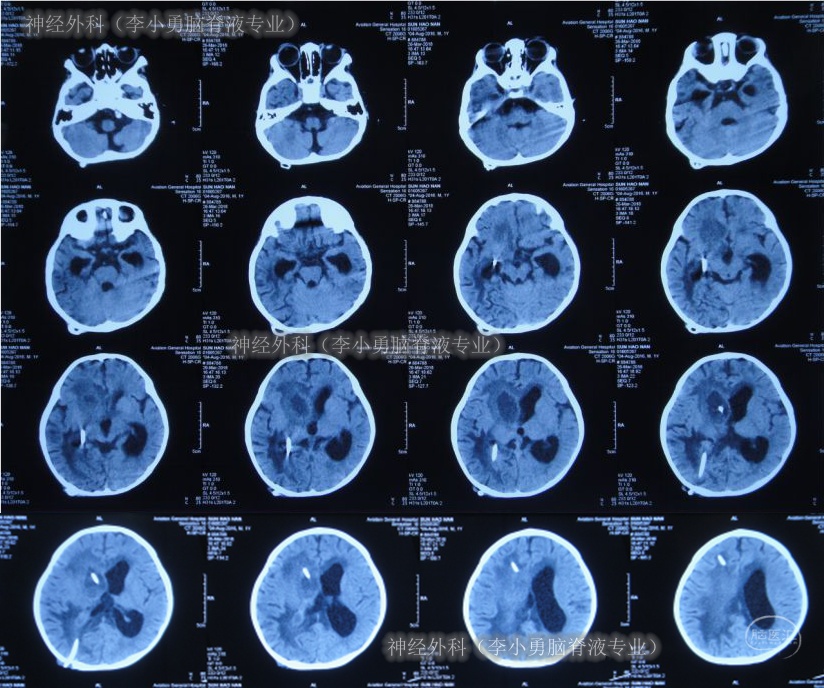

图-10:2018年3月13日腰颈腹部影像 2018年3月15日(右侧脑室腹壁外引流术后19天),复查头CT示脑室系统扩张,伴脑室旁水肿(图-11);再次加用两性霉素B。

图-11:2018年3月15日头颅CT

2018年3月16日(右侧脑室腹壁外引流术后20天),患儿病情加重呕吐变得更频繁,复查头CT示脑室系统扩张进一步增大(图-12)。

图-12:2018年3月16日头部CT

当天接受了经右额侧脑室穿刺Ommaya囊植入术,术后当天查头部CT示脑室内有2根管(图-13)。

图-13:2018年3月16日Ommaya囊植入术后头部CT